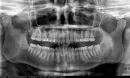

Я хочу поставить себе брекет-систему. После осмотра врач сказала, что обязательно нужно удалять зубы мудрости и далее ходить в брекетах минимум полтора года. У меня в наличии имеются рентгеновские снимки и заключение врача. Хотел бы понять, не разводят ли меня на ненужное лечение.

Хотел бы понять насколько это действительно так? Обязательно ли удалять зубы мудрости и обязательно ли ходить в брекетах столько времени?

Удаление восьмых зубов имеет место. Для 38-го отсутствует антагонист, а 18-й и 48-й для симметричности зубных рядов.